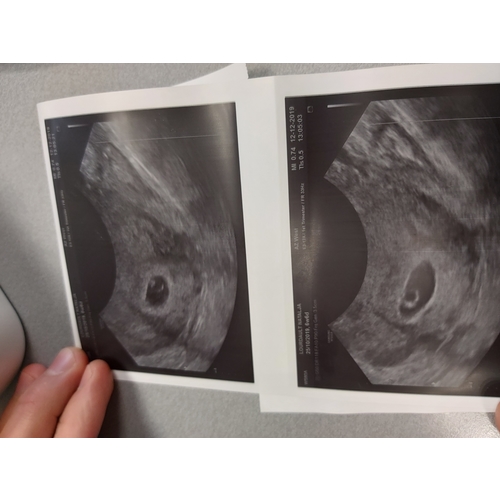

Ik was toch best angstig om te horen te krijgen dat er geen hartslagje te zien ging zijn....

Maar we hebben het in het dubbel mogen meemaken... wij zijn zwanger van een TWEELING!

Totaal niet verwacht, overdonderd met emoties maar ze zijn beiden zo welkom 🥰